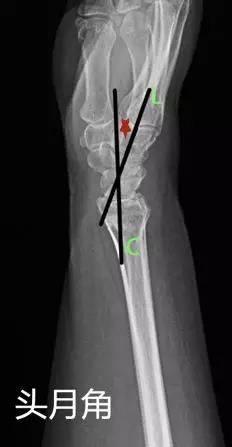

- 头月角:腕部侧位片上头状骨和月骨中轴线的夹角。

- 正常值:0°~15°

- 临床意义:>20°提示腕关节不稳。